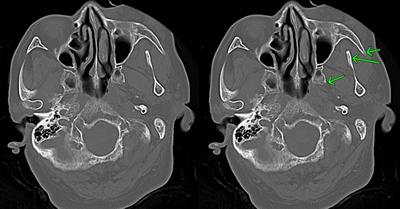

頭蓋骨陥没骨折

頭蓋骨陥没骨折とは、頭蓋骨が内側に陥没陥没する病態です。頭蓋骨の内側にある脳を傷つけるため、高確率で外傷性てんかんが発生します。

外傷によって脳の実質部に残った瘢痕を除去するためには、手術によって摘出するほかありません。

この瘢痕部が時間をかけて、過剰興奮してしまうようになり、外傷性てんかんが発症するものと考えられています。

発作を繰り返すことにより周辺の正常な脳神経細胞も傷つき、性格変化や知能低下の精神障害となり、高度になると痴呆や人格崩壊にまで至ります。